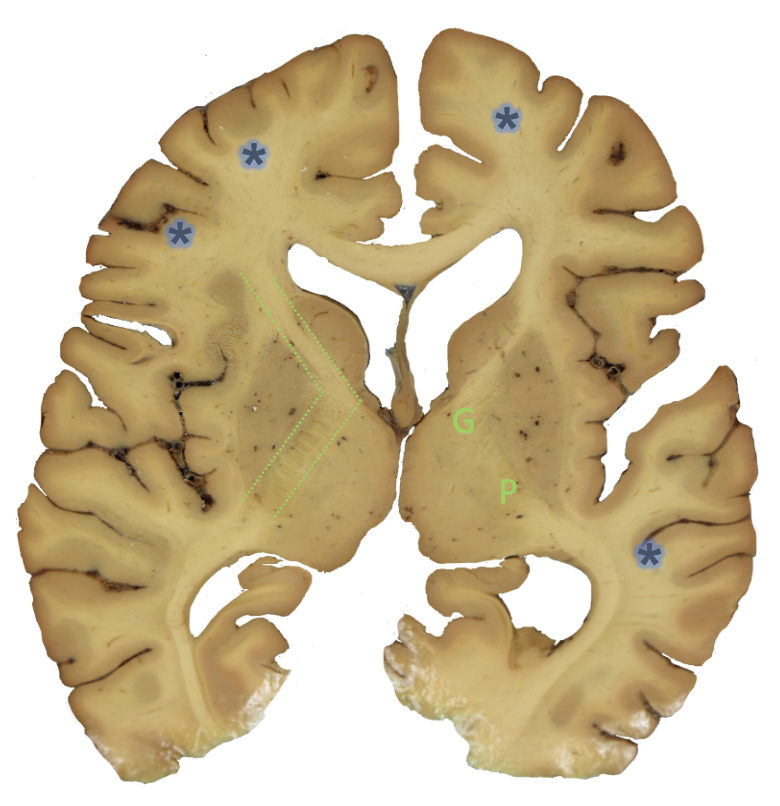

<p><strong>ic?</strong></p>

subcortical white matter

<p><strong>g?</strong></p>

genu

<p><strong>p?</strong></p>

posterior limb

• internal capsule

• _______: carries motor axons to trunk and extremities

• continues as the crus cerebri

• _____: carries fibers that go to brainstem

• ______ tracts: motor cortex to skeletal muscles of head and neck to coordinate precise, voluntary movements, travel in this area

posterior limb, genu, corticonuclear